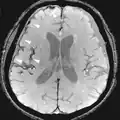

Agentes de contraste

A ressonância magnética para imagens de estruturas anatômicas ou fluxo sanguíneo não requer agentes de contraste, pois as propriedades variáveis dos tecidos ou sangue proporcionam contrastes naturais. No entanto, para tipos de imagem mais específicos, os agentes de contraste intravenosos mais utilizados são baseados em quelatos de gadolínio.[18] Em geral, esses agentes se mostraram mais seguros do que os agentes de contraste iodados utilizados na radiografia ou TAC. As reações anafilactóides são raras, ocorrendo em cerca de 0,03 a 0,1%.[19] De particular interesse é a menor incidência de nefrotoxicidade, em comparação com os agentes iodados, quando administrados em doses usuais. Isto fez uma varredura de ressonância magnética contrastante uma opção para pacientes com insuficiência renal, que de outra forma não seriam capazes de ser submetidos a TAC com contraste.[20]